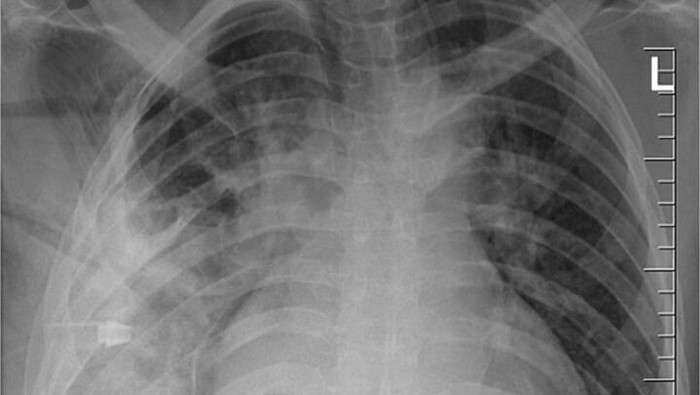

“Pencitraan awal dengan radiografi dada lateral menunjukkan adanya benda logam yang tertahan di bagian tengah toraks, dengan kekeruhan di sekitarnya yang kemungkinan merupakan hematoma terlokalisasi kronis atau yang sudah sembuh, atau fibrosis pascatrauma, yang merupakan sekuel dari luka tusuk pasien,” tulis para dokter. (Foto: Journal of Surgical Case Reports).

Saat perkelahian itu terjadi delapan tahun lalu, rumah sakit tempat ia dirawat tidak memiliki fasilitas radiologi. Karena setelah lukanya sembuh ia tidak lagi mengeluh sakit, tidak ada pemeriksaan lanjutan yang dilakukan. Adapun Nanah yang keluar ternyata merupakan akibat dari penumpukan jaringan mati di sekitar benda asing tersebut. (Foto: Journal of Surgical Case Reports).